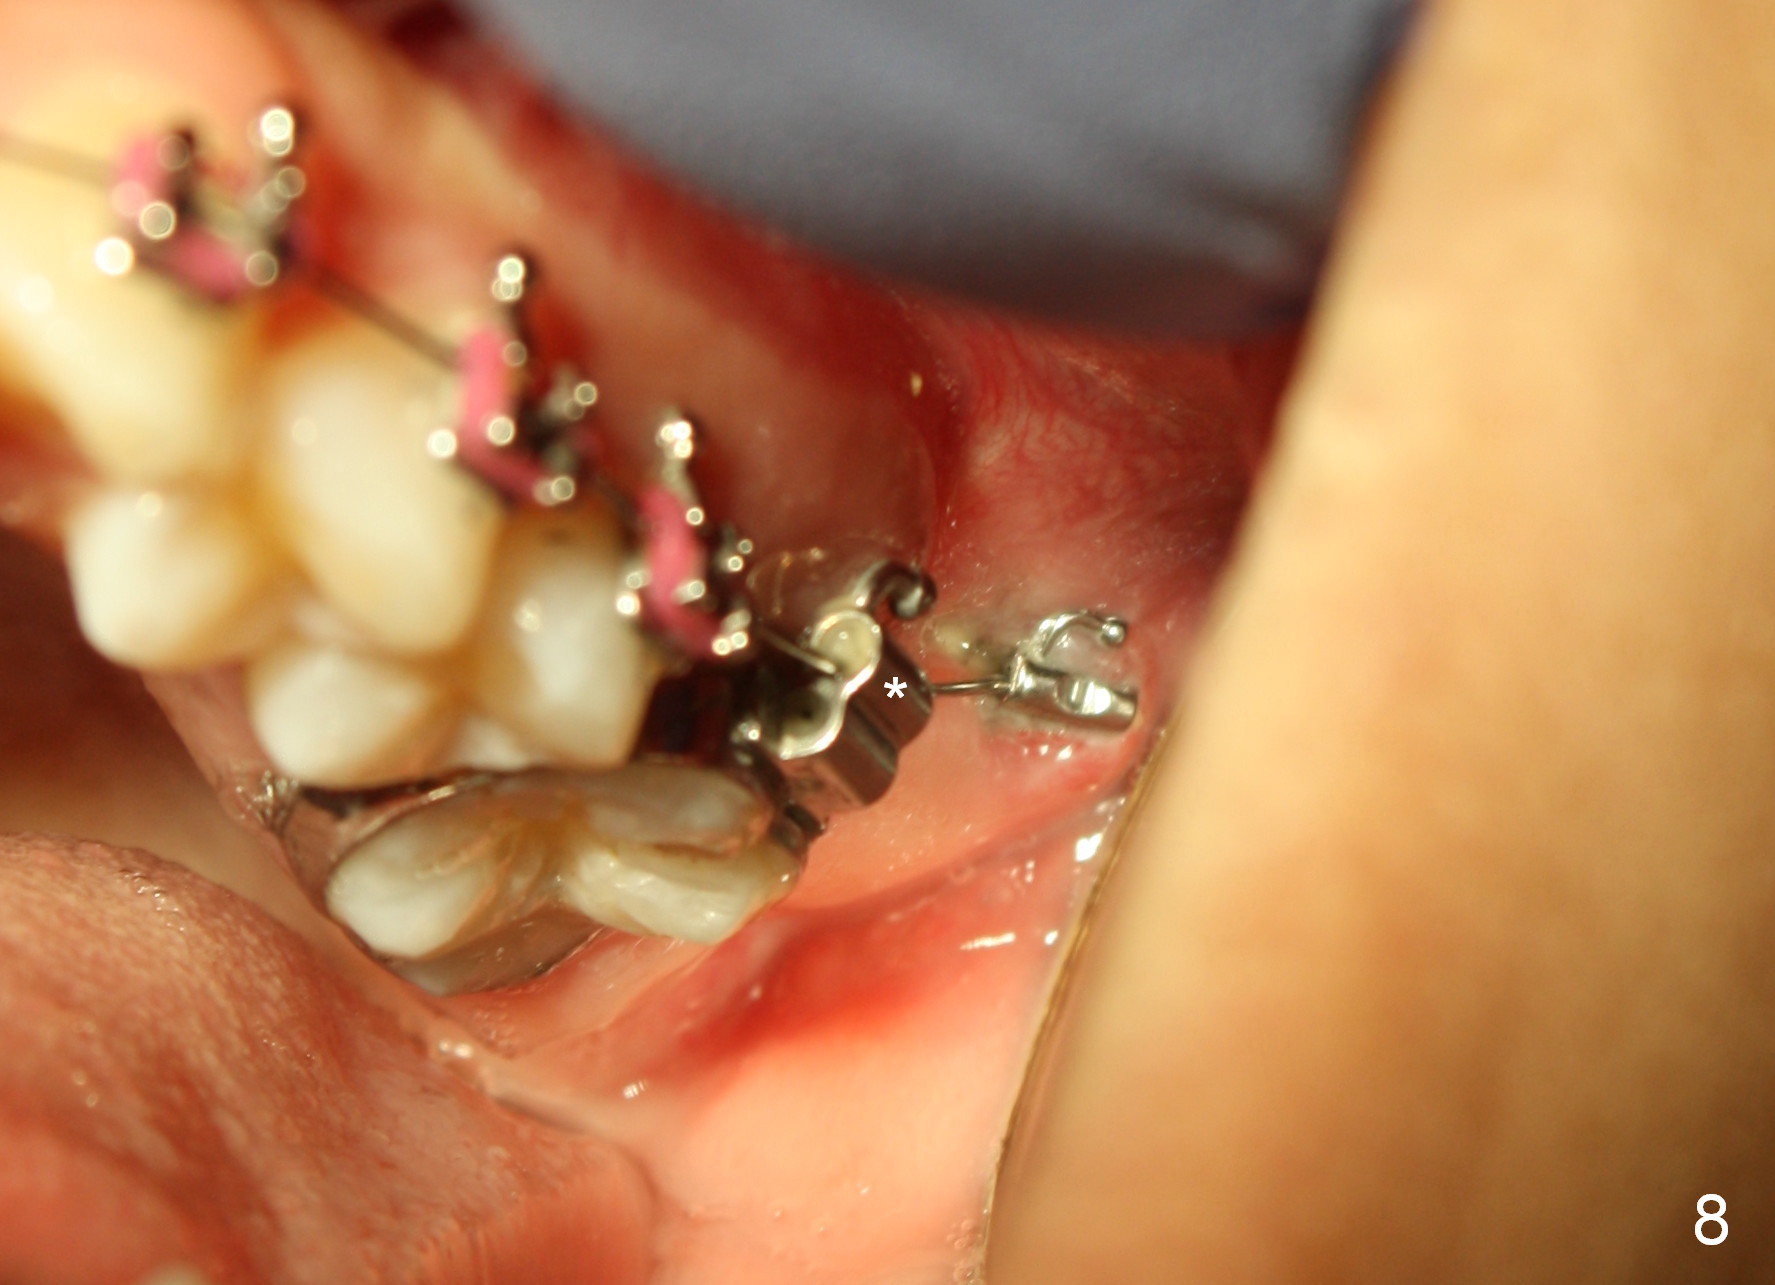

The distobuccal cusp of the tooth is subgingival 8 months post banding (Fig.6 (mirror view) *). A 2nd surgery is performed to expose the gold chain (Fig.7 <) and a bracket is placed. With arch wires, eruption of the impacted tooth is quickened (Fig.8). Later a 3rd minor surgery is done to place a lingual button to facilitate lingual cusp eruption. Finally a band has to be placed at #15. Treatment finishes in 2 years. The patient (15 years 2 months old) returns for follow up 3 months post debanding (Fig.9). There is no bone loss around the tooth #15 2 years 4 months post de-banding (Fig.11, as compared to the tooth #2 (Fig.10)).